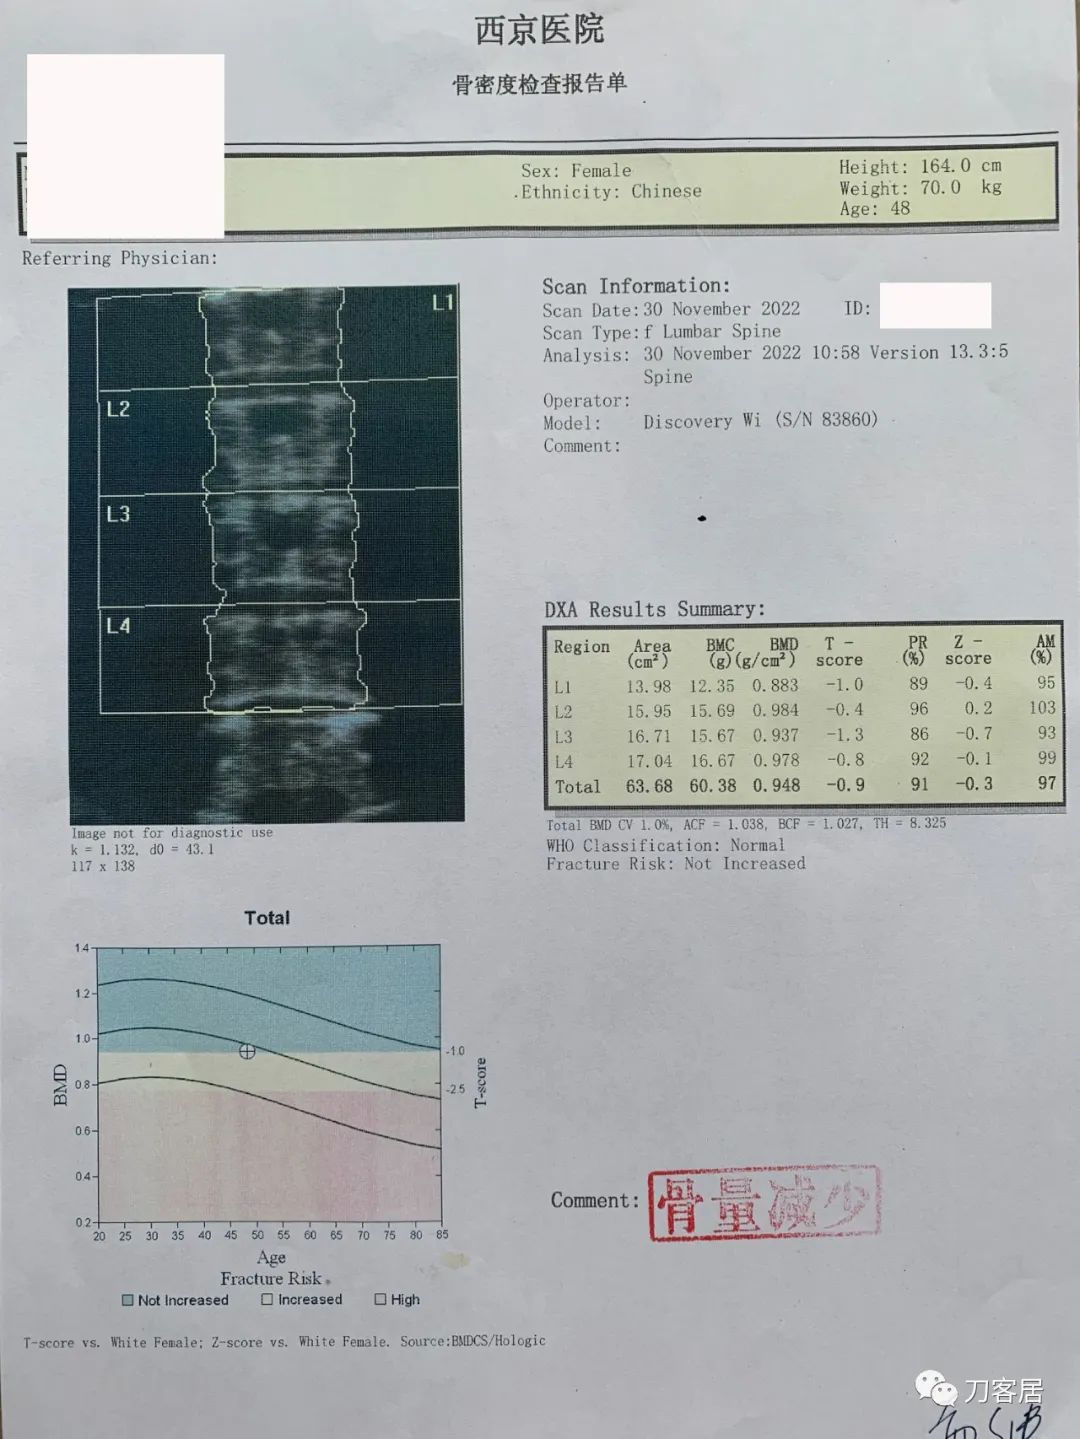

辅助检查:自带腰椎MRI提示未见严重的椎间盘突出及椎管狭窄,骨密度提示骨量减少,T值最低-1.3。

图5. 20221130西京医院骨密度检查结果